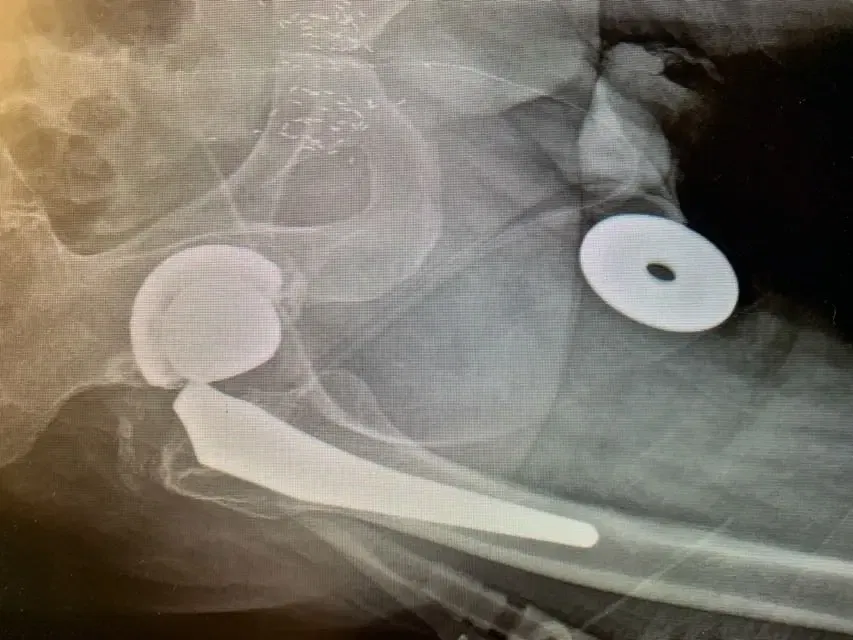

Las radiografías simples revelaron un adelgazamiento y «penciling» del cuello del componente femoral, lo que indicaba una probable corrosión por rozamiento en la muñonera, también conocida como «muñonosis». De hecho, las radiografías indicaban que la unión estaba tan corroída que se había fracturado. Investigaciones posteriores revelaron que el tipo de componente utilizado en la primera operación de sustitución presentaba este fenómeno en mayor proporción que otros, aunque esto no se sabía en aquel momento.

Utilizamos el mismo abordaje quirúrgico que el cirujano anterior, en este caso el abordaje lateral, y expusimos la articulación de la cadera de forma cuidadosa y meticulosa. Una vez completada esta operación, dislocamos la cadera y recuperamos el componente de la cabeza femoral, lo que reveló que el cuello del componente femoral había estado pistoneando dentro del componente de la cabeza, lo que había provocado que se erosionara hasta parecerse a la punta de un lápiz.